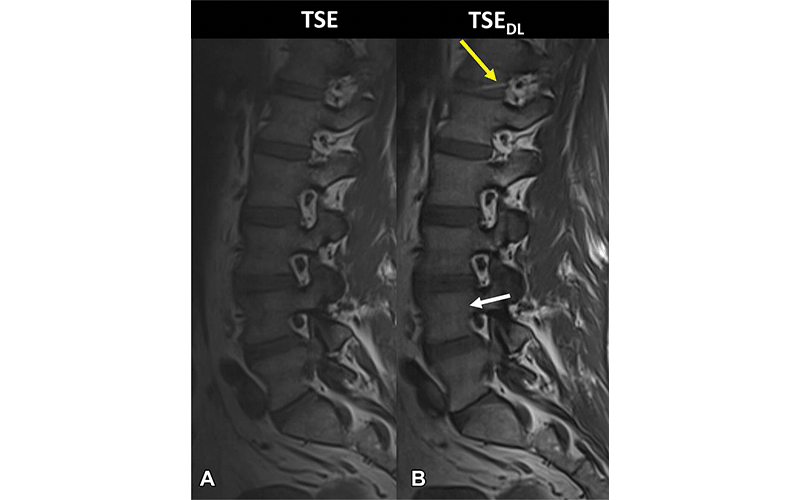

Noncontrast MRI scans at 3 T in a 46-year-old male participant who presented with acute onset of low back pain. (A) Sagittal T1-weighted image acquired with standard fully sampled turbo spin echo (TSE) shows no relevant artifacts. (B) Sagittal T1-weighted image acquired with deep learning–reconstructed TSE (TSEDL) shows characteristic banding artifacts with a streaking pattern aligned with the phase-encoding direction (white arrow). The same image illustrates a white band on the intervertebral disk T12-L1 (yellow arrow), which is an aliasing artifact due to the higher parallel acceleration factor. https://doi.org/10.1148/radiol.212922 © RSNA 2022

To learn more, researchers in Germany compared DL-reconstructed TSE (TSEDL) with standard TSE in 50 participants. Each participant underwent MRI with each technique. Five experienced radiologists evaluated the images.

DL-reconstructed TSE acquisition was found to be interchangeable with standard TSE for detecting various abnormalities of the spine at MRI. The DL-reconstructed TSE sequences reduced the median total acquisition time from 328 seconds to 100 seconds for a 70% reduction in examination time. No evidence of a difference was found between standard TSE and TSEDL regarding frequency of major findings, overall image quality, or diagnostic confidence.